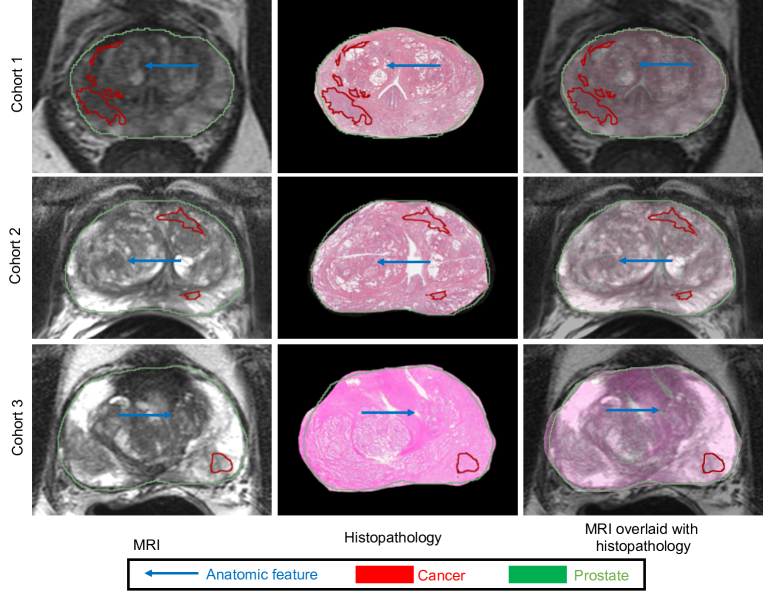

Figure 7 shows the registration results of three patients with large cancerous regions (one from each cohort).

Figure 7: Registration results for three different subjects (one from each cohort) using the proposed ProsRegNet deep learning registration pipeline. The MRI slices were chosen as the fixed images. (Left) MRI, (Middle) registered histopathology image, (Right) MRI overlaid with registered histopathology image. Cancer labels from the histopathology images were mapped onto MRI using estimated transformations from image registration.

The prostate boundaries on the MRI and the histopathology sections appeared well aligned for all three subjects, suggesting that the ProsRegNet pipeline achieved accurate global alignment of the prostate. Anatomic regions of the prostate on the MR and the histopathology images were also well aligned. Accurate alignment of anatomic regions indicates that the ProsRegNet pipeline has achieved promising alignment of local prostate features. The results in Fig. 7 demonstrate that our ProsRegNet pipeline generalizes across cohorts even if they were not part of the training, showing accurate registration for images from different cohorts acquired by different protocols. Our accurate alignment of the histopathology and MRI images suggests that we can carefully map the cancer labels in the histopathology images to the corresponding MRI slices using the estimated transformations.